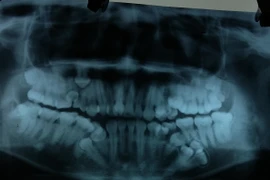

Bào chế thành công thực phẩm chức năng ngăn ngừa bệnh răng miệng ảnh 1Ảnh chỉ có tính minh họa. (Nguồn: conacytprensa.mx)